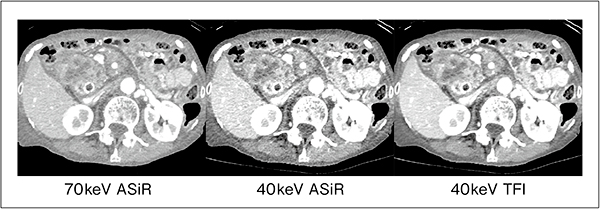

そこで,GEは,ディープラーニングを用いて,低ノイズかつ自然な質感を両立した画像を再構成することが可能なTrueFidelity Image(以下,TFI)を開発した。TFIは米国食品医薬品局(FDA)に承認された,世界で初めてのディープラーニング再構成法である。TFIをGSIと併用することにより,ノイズの影響を受けやすかった低keV画像などが非常に使用しやすいものとなり,病変部の視認性をより向上させることが可能となった(図2)。また,ノイズを大幅に低減することにより,低keVとnarrow windowの組み合わせによる低コントラスト強調に特化した画像を提供することも可能である(図3)。

図2 低keV画像におけるASiRとTFIの比較(膵頭部腫瘍)